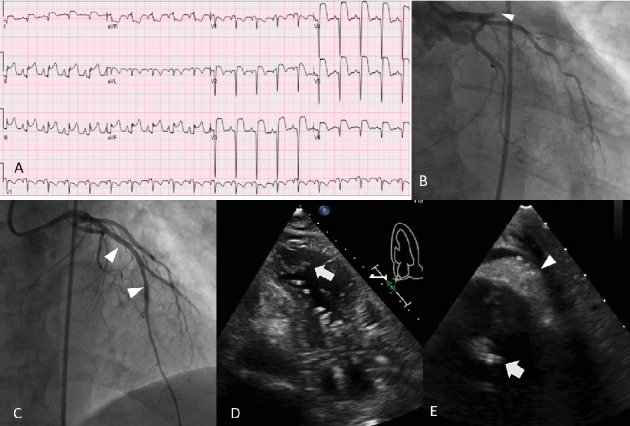

Mechanical circulatory support devices, such as the Impella catheter (Abiomed, Danvers, Massachusetts), continue to become more commonplace in patients undergoing high-risk percutaneous coronary intervention (PCI) or those in cardiogenic shock. Thrombus in the left ventricle is a contraindication to Impella placement. Here, we present a patient with an anterior ST elevation myocardial infarction who underwent primary PCI with subsequent development of cardiogenic shock followed by Impella placement, who then later developed an LV thrombus. The Impella was removed after placement of a Sentinel cerebral protection device (Boston Scientific, Massachusetts). The left carotid filter of the Sentinel captured a thrombus fragment. The patient did not have any neurological compromise. This case represents the first report of actual capture of LV thrombus by a Sentinel system in this context. The case suggests the potential value of the Sentinel cerebral protection device to lower the risk of an embolic event during Impella removal in selective clinical scenarios.